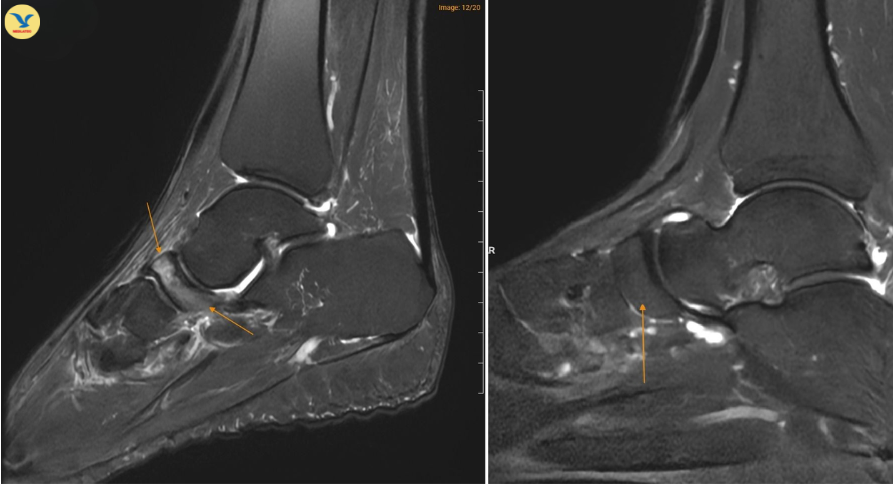

![]() |

| Hình ảnh MRI cho thấy xương ghe ở bệnh nhân mắc Hội chứng Müller–Weiss (bên trái) có vùng sáng hơn bất thường, trong khi xương ghe ở bàn chân bình thường (bên phải) có hình ảnh đồng nhất hơn. |